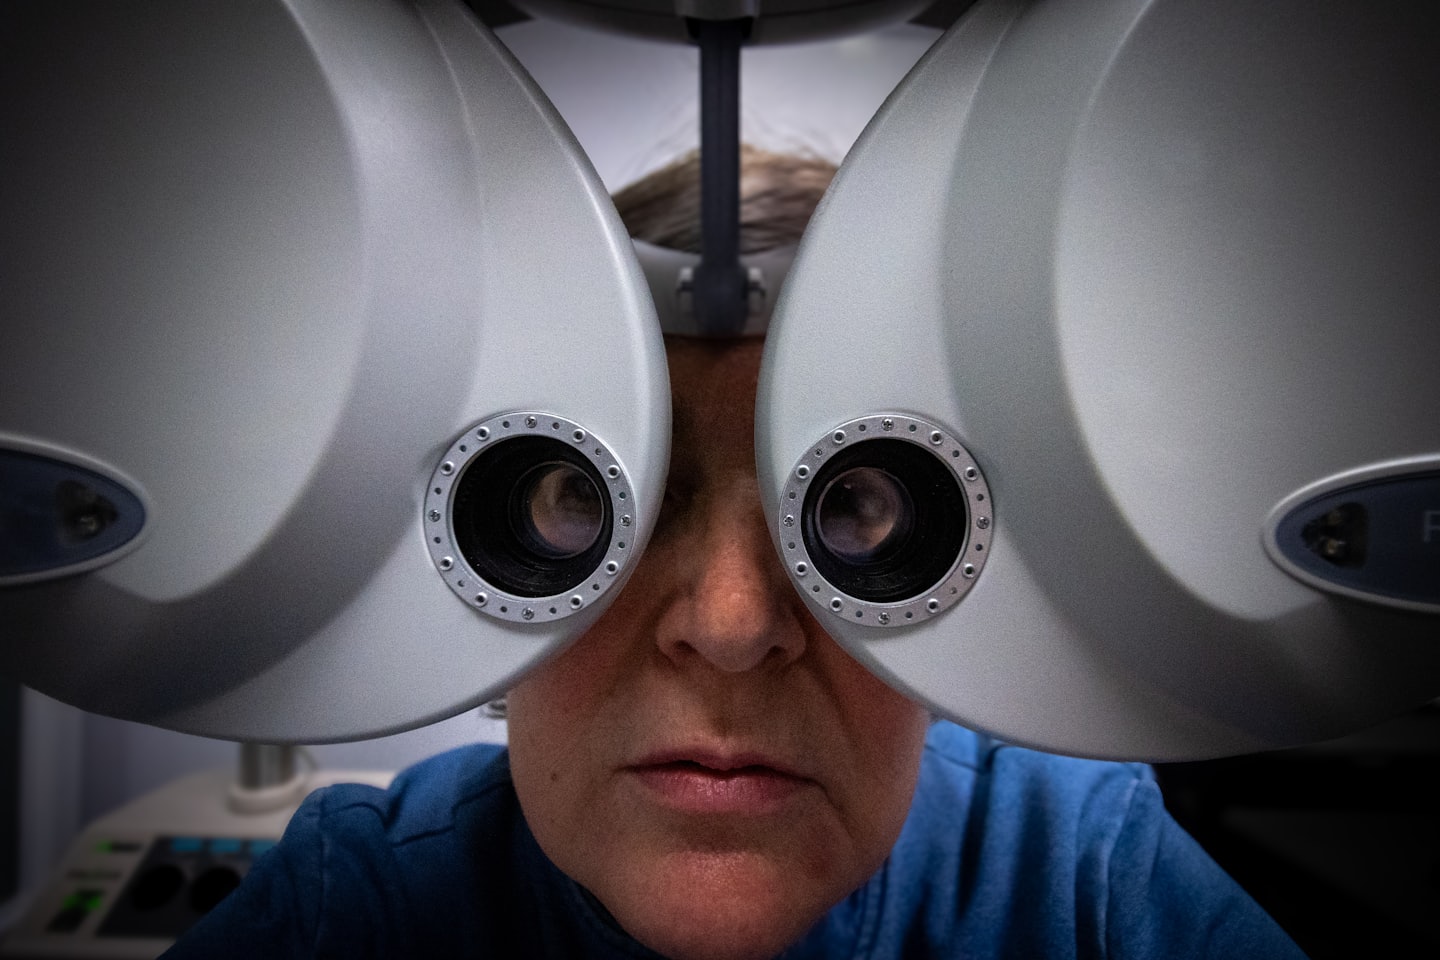

No consultório do Dr. Wanderson Vargas, oferecemos atendimento humanizado em oftalmologia, com diagnósticos precisos, tratamentos modernos e cirurgias avançadas para garantir a saúde dos seus olhos.

Cuidados oftalmológicos especializados com atenção humanizada

Conheça o compromisso do Dr. Wanderson Vargas com diagnósticos precisos, tratamentos modernos e cuidado atento, garantindo a saúde visual de cada paciente.

Conheça nossos serviços dedicados à saúde dos seus olhos, com atendimento humanizado e tecnologia de ponta.

Consulta Inicial

Realizamos uma avaliação detalhada para entender suas necessidades e planejar o melhor tratamento para sua visão.

Agende sua consulta com o Dr. Wanderson Vargas de maneira simples e rápida, garantindo um atendimento personalizado para sua saúde visual.

Cuidados oftalmológicos especializados com atenção humanizada

Conheça o compromisso do Dr. Wanderson Vargas com diagnósticos precisos, tratamentos modernos e cuidado atento, garantindo a saúde visual de cada paciente.

Conheça nossos serviços dedicados à saúde dos seus olhos, com atendimento humanizado e tecnologia de ponta.